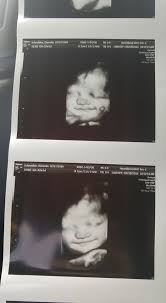

The 33rd week of pregnancy and the four weeks that follow mark a time of astounding growth as your baby reaches her ultimate birth weight. I have gained around 25 pounds at 33 weeks pregnant and am feeli. Your baby's team will talk to you about how you should monitor your baby and any care requirements. Find out how big your baby is in each week of pregnancy, using our fetal growth chart measurements of average length and weight. According to march of dimes , a baby who weighs under 5 lb 8 oz at birth has a low birth weight. Their rate of growth will gradually slow down as they. How much weight does a baby put on during pregnancy from 33 weeks ? Searches may come from : #pregnancyat33rdweek #weekbyweekpregnancy #33rdweek #symptoms of33rdweek #ultrasoundat33rdweek #babyat33rdweek. At 33rd week of pregnancy what should be the precautionary measures at 33rd week of pregnancy and many more. It is common for babies to lose around 10% of their weight shortly after birth. He weighs more than 4¼ pounds and is still gaining weight at a rate of about half a pound a week. At 33 weeks pregnant, there's just 7 weeks left until your baby's due date and you're in month 8 of your pregnancy!

Baby weighed as appropriate for gestational age. Im 33 weeks, must have put on quite a bit but i'm just focusing on eating the best i can (which is not. Your baby's brain can now control its body temperature. Weight of a human baby at birth. He weighs more than 4¼ pounds and is still gaining weight at a rate of about half a pound a week. Generally a baby is expected to double in weight from 32 to 40 weeks. Most babies with low birth weight or very low birth weight were born prematurely. How much weight does a baby put on during pregnancy from 33 weeks ? Your baby is in his final stages of development when you're 33 weeks pregnant! Even with the broad range that defines healthy weights for various infant ages, there may be times when you it may take weeks for your baby to gain weight so don't worry. At 33rd week of pregnancy what should be the precautionary measures at 33rd week of pregnancy and many more. Pregnancy weight gain should be in accordance with the bmi of the mother at the time of conception. Thereof, how much weight do preemies gain per day?